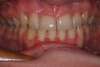

Jeune adulte traitée en technique linguale

S-Fin de traitement